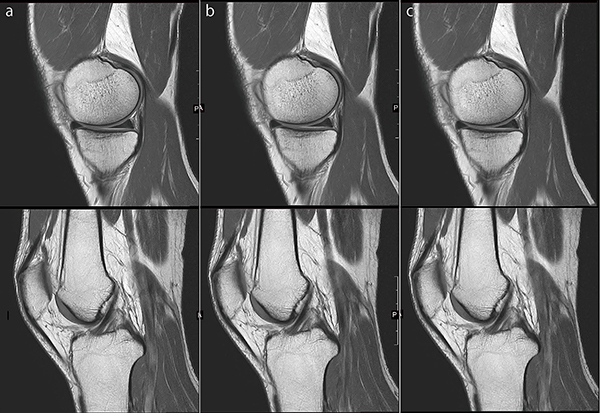

●膝関節PDWI

図10 aは,IP-RAPIDを使用していない画像です。それに対して図10 b,cはIP-RAPIDを使用して,撮像時間を維持したまま空間分解能を向上しています。頭部MRAと同様に,空間分解能を向上させるためにはFreq/Phaseを大きくする必要があります。そしてIP-RAPIDを活用することで,その結果生じる撮像時間の延長やSNR低下の影響を低減させることができます。

図10 膝関節PDWI

a:IP-RAPID off, Phase=1.6, Freq/Phase=288×288, scan time=2:58

b:IP-RAPID on, Phase=1.8, IP-Recon=Light, Freq/Phase=320×320, scan time=2:58

c:IP-RAPID on, Phase=2.0, IP-Recon=Medium, Freq/Phase=352×352, scan time=2:56